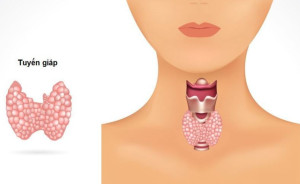

Theo các bác sĩ, việc quyết định mổ cắt tuyến giáp cần được tính toán kỹ lưỡng, dựa trên tình trạng sức khỏe tổng thể. Bởi sau mổ cắt tuyến giáp người...